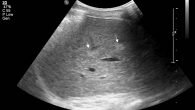

Одним из самых распространенных абдоминальных (брюшных) исследований является ультразвуковое. Его часто назначают, чтобы обследовать печень. Размеры печени в норме по УЗИ различны, и зависят от возраста, пола, телосложения. Что касается результатов, их верная расшифровка поможет правильно поставить диагноз и своевременно назначить грамотное лечение.

- Структура, контуры. В норме орган гладкий, ровный, контуры четкие, структура однородная, края острые, угол левой доли — 45 градусов, правой — 75, структура ткани однородная. Если на поверхности есть бугры или посторонние образования, можно говорить о развитии онкологических процессов или эхинококкозе (поражении гельминтами).

- Эхогенность. Это акустические свойства органа (поглощение звуковых волн и звукопроводимость). Чем выше содержание жидкости в органе, тем ниже эхогенность, а значит, можно говорить о циррозе, эндокринных заболеваниях, нарушенном обмене веществ или о том, что пациент принимал большое количество медикаментов.

- Зернистость. Ее придают структурные единицы органа — печеночные доли (дольки), между которыми расположены желчные и кровеносные протоки. У здоровой печени структура мелкозернистая, ее изменение говорит о воспалительном процессе.

- Размеры. Один из важных показателей состояния органа. Также измеряют КВР — косой внутренний размер; большая доля печени имеет особое значение для измерения КВР. Ниже приводится таблица, где указаны нормальные показатели размеров печени.